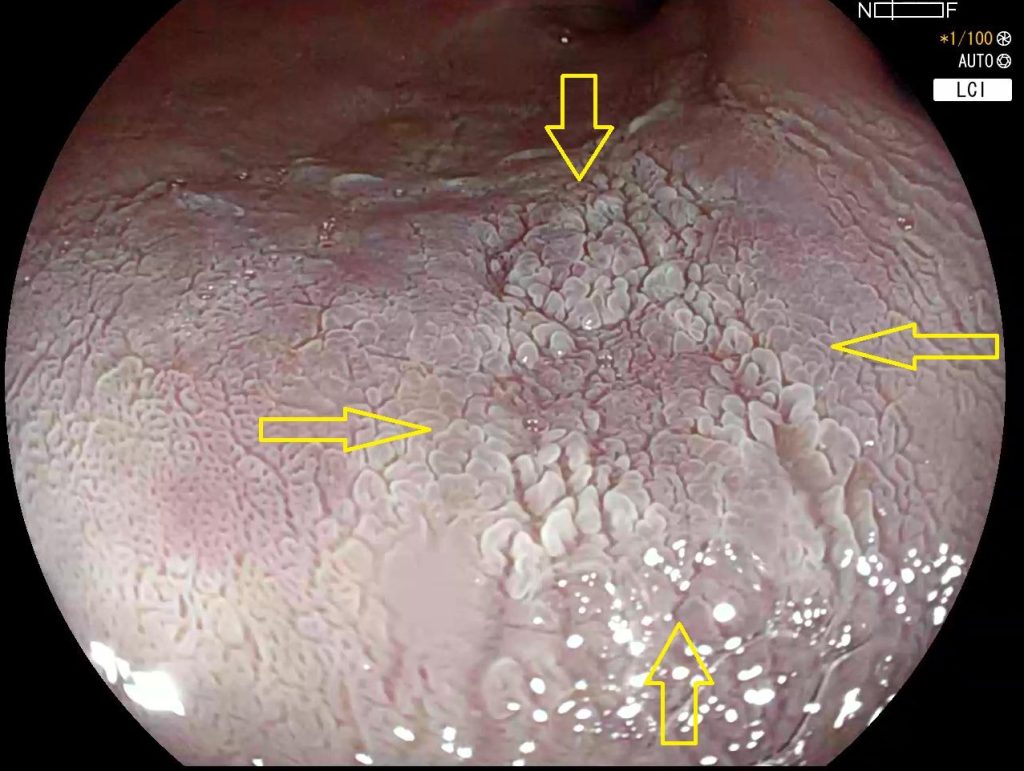

El riesgo es particularmente elevado en pacientes con esófago de Barrett, donde el tejido esofágico ya ha sufrido cambios metaplásicos (las células normales de un tejido se transforman en otro tipo de células que no suelen estar en esa zona).

La gravedad del riesgo está relacionada tanto con la concentración de la bilis como con el tiempo de exposición, siendo especialmente importante en áreas donde la bilis tiende a acumularse por efecto de la gravedad.

Esta relación subraya la importancia de:

• La detección temprana del reflujo biliar.

• El seguimiento regular de pacientes con esófago de Barrett.

• La implementación de estrategias preventivas.

• La vigilancia especial en pacientes con factores de riesgo adicionales.

Neoplasia precoz esofágica en paciente con esófago de Barrett. Cromoendoscopia con ácido acético.